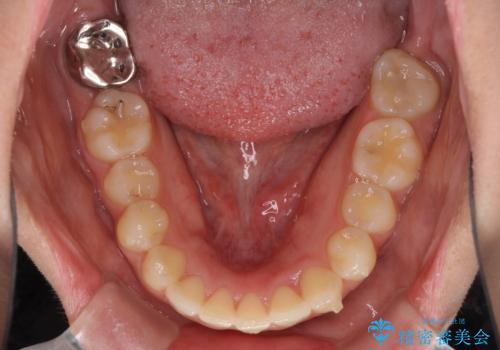

また、下顎骨の右側変位による右側臼歯の咬合を改善させるよう試みることとしました。

右側の咬合改善を目標に様々な手法を用いましたが、骨格的なズレによる不正咬合はインビザラインでは改善することができませんでした。